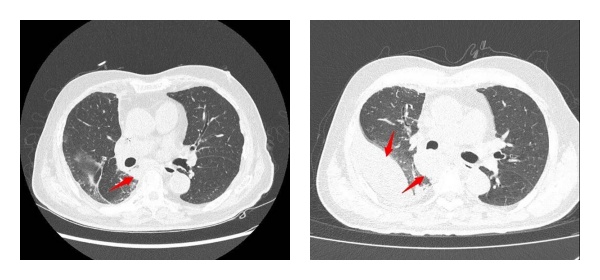

针对该患者病情特点,胸外科团队制定了化疗联合免疫治疗的个体化方案。2025年11月下旬及12月中旬,患者分别完成两个周期的白蛋白紫杉醇+卡铂联合帕博利珠单抗治疗。治疗后患者胸闷、喘憋等症状显著缓解,影像学复查显示右肺门肿瘤及胸膜多发转移病灶均明显缩小,治疗效果显著。目前患者整体病情得到有效控制,已出院继续接受恢复性治疗。